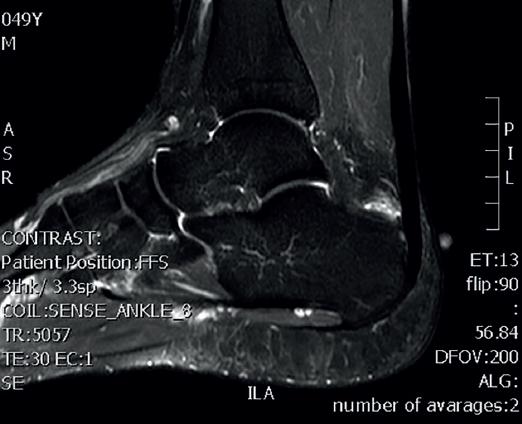

Magnetic resonance imaging

Magnetic resonance imaging (MRI) allows us to evaluate the presence of intratendinous injuries, fluid collections, the appearance of the bursae, bone edemas in the posterior tuberosity, and to establish the differential diagnosis with other disease conditions(22)(Figure 5). If the plain radiographs and ultrasound findings are conclusive, MRI is not essential. In the absence of an experienced ultrasound operator, or if there are doubts after ultrasound regarding the presence of disease in the tendon and bursa, MRI is very useful.

Figure 5. Magnetic resonance imaging. Retrocalcaneal bursitis. Fluid in the retrocalcaneal recess without signs of degenerative tendinopathy.